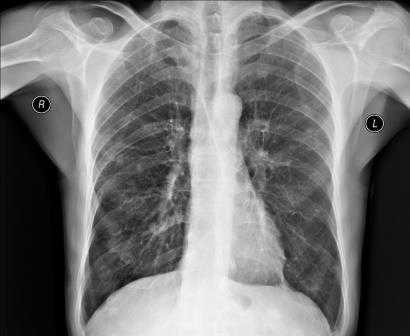

Рентгенография грудной клетки - это метод диагностики, позволяющий получить изображение органов грудной полости с помощью облучения рентгеновыми лучами. Различные ткани организма в зависимости от своей плотности по-разному пропускают рентгеновы лучи, а значит, по-разному отображаются на снимке (рентгенограмме).

Рентген грудной клетки дает возможность изучить костные структуры (ребра, грудину, позвоночник), легкие, плевру, бронхи и трахею, сердце и средостение, а также оценить состояние мягких тканей этой области.

Чаще всего врачу требуется рентгенограмма в прямой проекции, изображение в боковой проекции нужно значительно реже. При правильно проведённом обследовании четко заметны рёбра, сердце, органы дыхания, частично — кости плечевого пояса.

Рентгенография легких позволяет оценить их состояние размер, форму, структуру тканей, а также расположение прочих органов грудной клетки. Для получения наиболее полной информации о состоянии лёгких, врачу необходима рентгенограмма в 2 проекциях, где чётко просматривается лёгочная ткань, купола диафрагмы, тень сердца и органов средостения, кости позвоночника, плечевого пояса, грудины. Изображение различных органов и костей наложено друг на друга.

Для корректной расшифровки изображения необходимо четкое представление о том, как на рентгенограмме выглядят здоровые органы грудной клетки. К примеру, даже малозаметные затемнения, просветления, ассиметричный легочный рисунок может свидетельствовать о серьёзном заболевании. Регулярное проведение обследований позволяет выявить патологии на ранней стадии и незамедлительно приступить к лечению.

Органы и ткани человека по-разному реагируют на ионизирующее излучение: чем выше их плотность, тем светлее на снимке объект. Выполнение рентгенографии грудной клетки позволяет изучить мягкие ткани, кости этой части тела и анатомические структуры, находящиеся в исследуемой полости (легкие, плевру, средостение).

В зависимости от показаний пациенту может быть назначен обзорный или прицельный рентген грудного отдела. В первом случае получают изображения всех органов грудной клетки. На снимке обзорной рентгенографии хорошо видны дыхательные пути, лимфоузлы, сосуды, бронхи, трахея, легкие и сердце. Прицельная рентгенография направлена на исследование конкретного органа или его части и обеспечивает оптимальное изображение патологического очага для диагностики.

После получения изображения рентгенолог делает заключение и краткое описание снимка для врача, направившего пациента на обследование. В записи указывается, как расположено сердце, его размер (увеличенный или нормальный), какова его паренхима. Кроме того описывается состояние и остальных внутренних органов грудной клетки - легких, бронхов, сосудов и лимфатических узлов. Если снимок показал наличие посторонних предметов, затемнений или новообразований, это также отражается в заключении рентгенолога.

Во время расшифровки полученного рентгеновского снимка, прежде всего, оценивается качество изображения, а значит, и насколько правильно осуществлена процедура. Если рентгенография была сделана в неверной проекции и снимок имеет неточности, то заключение на его основании сделать достаточно сложно. При рентгене легких, например, оценивается размер легких, их форма, структура тканей и легочных полей, состояние воздушности и расположение внутренних органов.

Если у пациента пневмония, на снимке будут видны ярко выраженные отклонения от нормы - интенсивные дополнительные ткани как на прямой, так и на боковой рентгенограмме. Присутствие на снимке особой прикорневой формы, напоминающей по виду крылья бабочки, говорит о венозном застое в области малого круга. На отечность легочной ткани будут указывать неравномерные хлопьевидные затемнения на изображении.